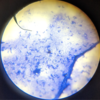

Giardia sp.: Trophozoite

Containing 2 nuclei

Giardia sp.: Trophozoites